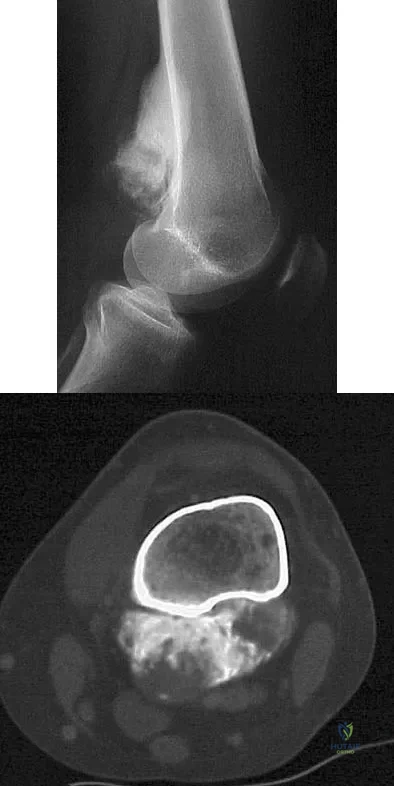

A 23-year-old woman has had vague left knee pain for the past 6 months. A radiograph and CT scan are shown in Figures 50a and 50b. What is the most likely diagnosis?